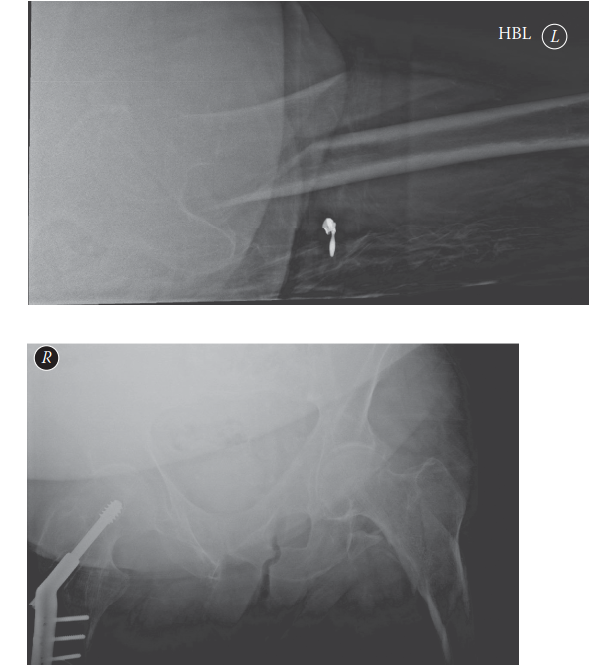

Radiographic Assessment:

- Standard Views: AP pelvis, AP and lateral views of the entire affected femur (including hip and knee joints) are mandatory. These allow assessment of fracture pattern, comminution, and pre-existing deformities or hardware.

- Contralateral Femur: AP and lateral views of the contralateral, uninjured femur can be invaluable for templating nail length, diameter, and assessing normal femoral bow.

- CT Scan: For complex comminution, especially with extension into the piriformis fossa or greater trochanter, a CT scan can provide detailed information about the fracture pattern, guide reduction strategies, and aid in implant selection. It can also rule out occult contralateral AFFs.

- Image Analysis: Assess the location of the lesser trochanter, the extent of comminution, the presence of a medial spike, and any pre-existing bowing of the femur. Identify the characteristic deforming forces (flexion, abduction, external rotation of the proximal fragment; adduction, shortening of the distal fragment).